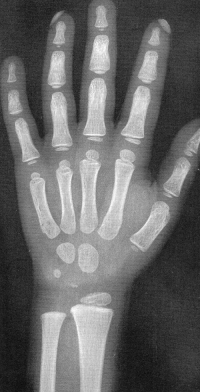

Sexo Feminino

Recém-Nascido

3 meses

Fonte: GREULICH, W.W. & PYLE, S.I.: Radiografic Atlas of Development of the Hand and Wrist. Stanford University Press, 2° edition, 1959.